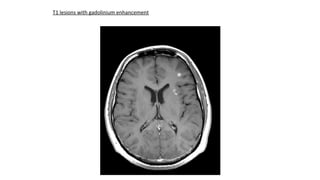

T1 lesions with gadolinium enhancement

T1 lesions withgadolinium enhancement